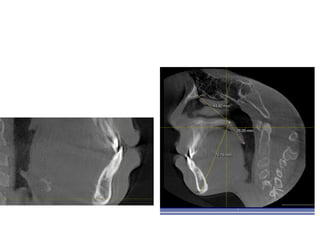

RME

• Maxillary constriction in particular has been

postulated to play a role in the pathophysiology

of OSA because of its association with low tongue

posture that may contribute to the orophayrnx

airway narrowing (Subtelny 1954).

• Pirelli et al. grouped 31 children with OSA and

followed them up to 4 months after RME

treatment. All of these children had their apnea-

hypoapnea index decreased while their mean

maxillary cross sectional width expanded to

about 4.5mm.